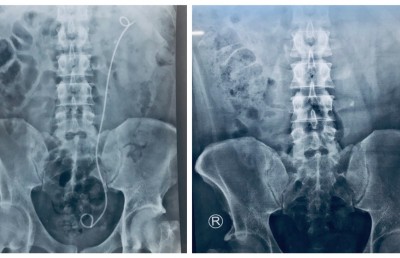

އަދީބުގެ އަނބިކަނބަލުން މަރިޔަމް ނަޝްވާ ވިދާޅުވީ އަދީބުގެ އޮޕަރޭޝަނަށް ފަހު އެތެރެހަށީގެ ޔޫރެޓްރާއަށް ސްޓެންޓެއް ލައްވާފައިވާ ކަމަށެވެ. އަދި އޮޕަރޭޝަނަށް ފަހު، އިންފެކްޓުވެ ހުން އައުމާ ގުޅިގެން އެންޓިބަޔޮޓިކްސް ދެމުން އަންނަ ކަމަށް ވެސް ނަޝްވާ ވިދާޅުވި އެވެ.

ނަޝްވާ ވިދާޅުވި ގޮތުގައި، އަދީބުގެ ހަށިގަނޑުގައި އުފެދުނު ހިލަ ނެގުމަށް ކުރި އޮޕަރޭޝަންގެ ސަބަބުން ހިލައިގެ އެއްބައި ހަށިގަނޑުން ބޭރުވިޔަސް، އަދިވެސް އެއް ބައި ހަށިގަނޑު ތެރެއިން ފެނެެެއެވެ.